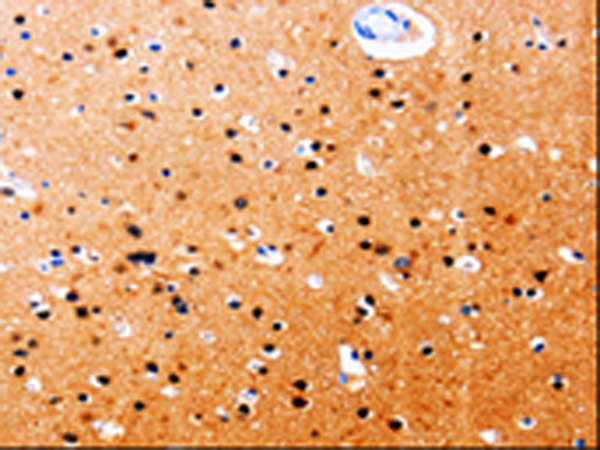

IHC positive control: |

Human brain and Human tonsil |

IHC Recommend dilution: |

25-50 |